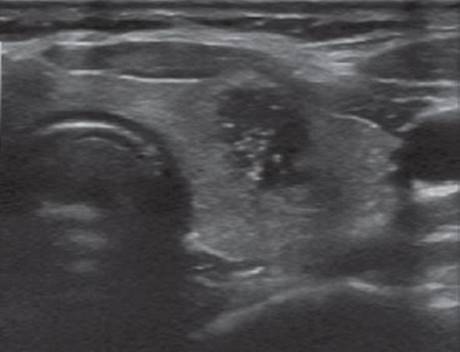

Ultrasound (U/S) is the imaging of choice for a newly diagnosed thyroid nodule. Ultrasound may assess nodule size, location, and other concomitant thyroid pathologies as well as the cervical lymph nodes. Ultrasonic features suspicious for malignancy include hypoechogenicity, microcalcification, irregular margins, chaotic vascular patterns, as well as extracapsular invasion and lymph node involvement. Figure 1 demonstrates the appearance of a malignant nodule on U/S.

FIGURE 1 • A malignant thyroid nodule. The nodule appears heterogeneous, cystic, hypoechoic, irregular margins, and microcalcifications are present.

The patient’s U/S demonstrated a 3.2-cm right thyroid lobe nodule. The nodule was hypoechoic and complex with some microcalcifications. In this patient, FNAB identified a follicular neoplasm.